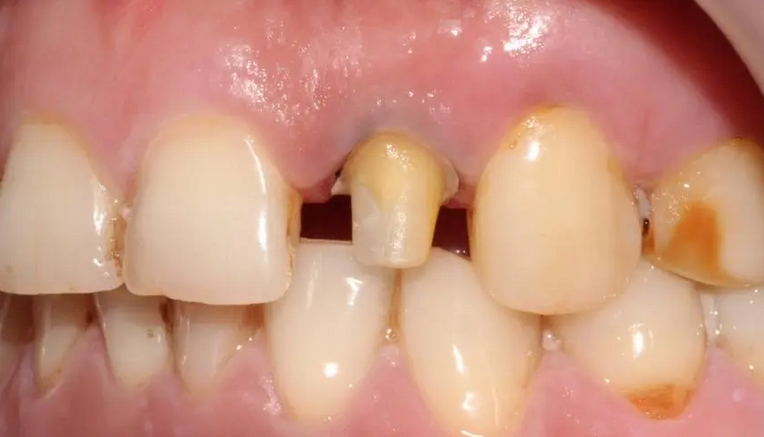

三根车针,六步完成——快速磨牙全冠预备!